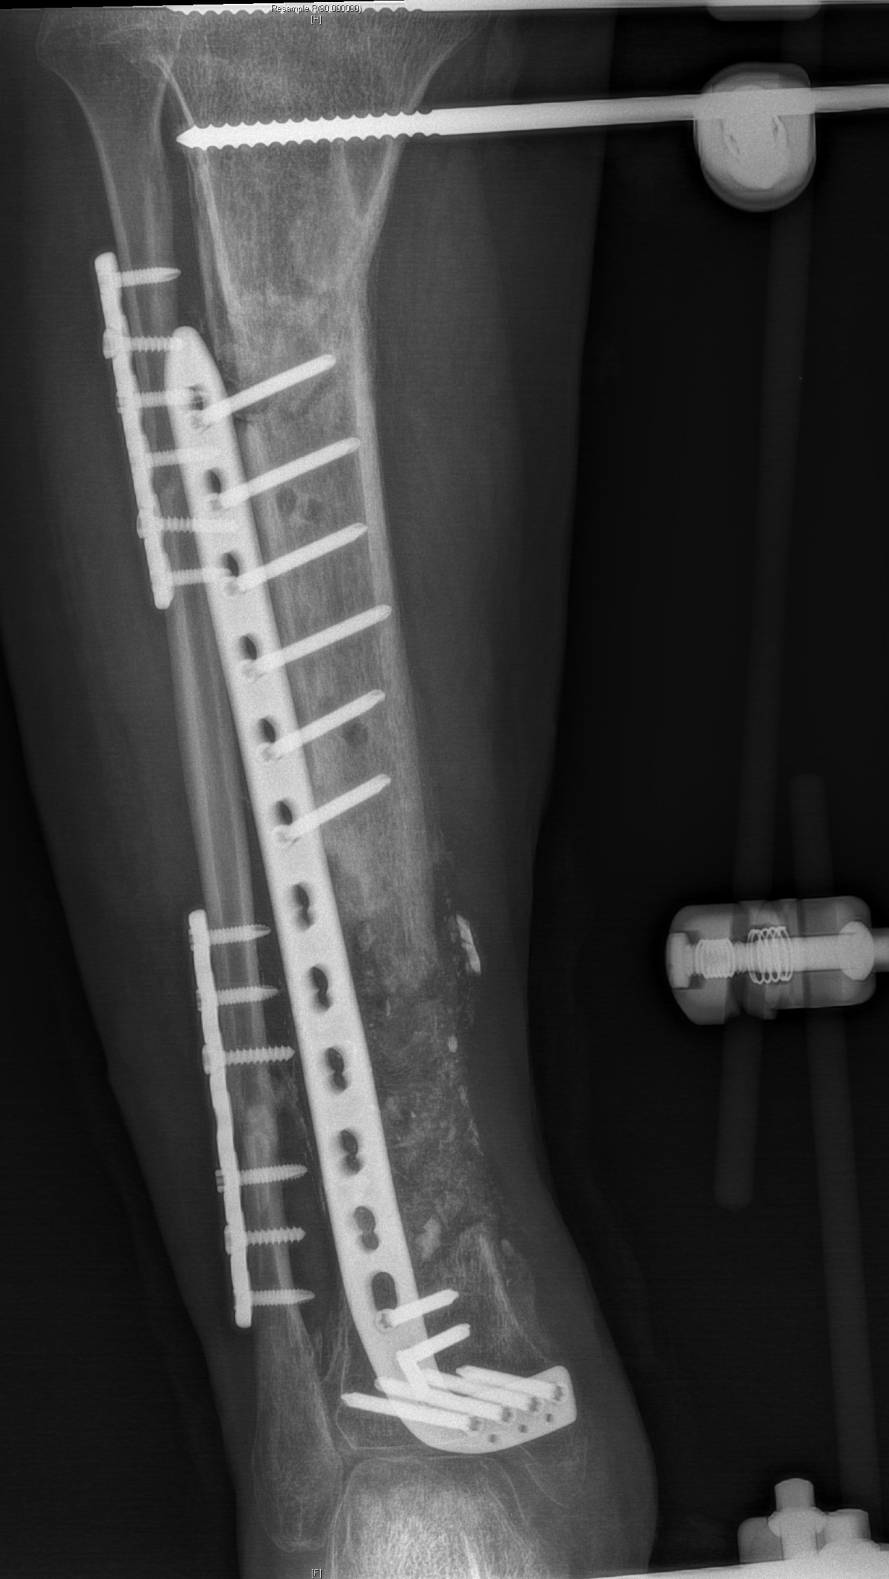

2、骨缺损重建

3、骨愈合

徐杨主任医师介绍,对于肢体毁损伤后期合并感染患者,保肢最大的难题是清创及骨与软组织重建,masquelet技术能够形成骨水泥诱导膜,不但能起到屏障作用,还含大量微血管,丰富血供,并能分泌各种促骨生长因子,具有成骨快、愈合率高的优点。尤其适合治疗长节段、严重感染性骨缺损病例。